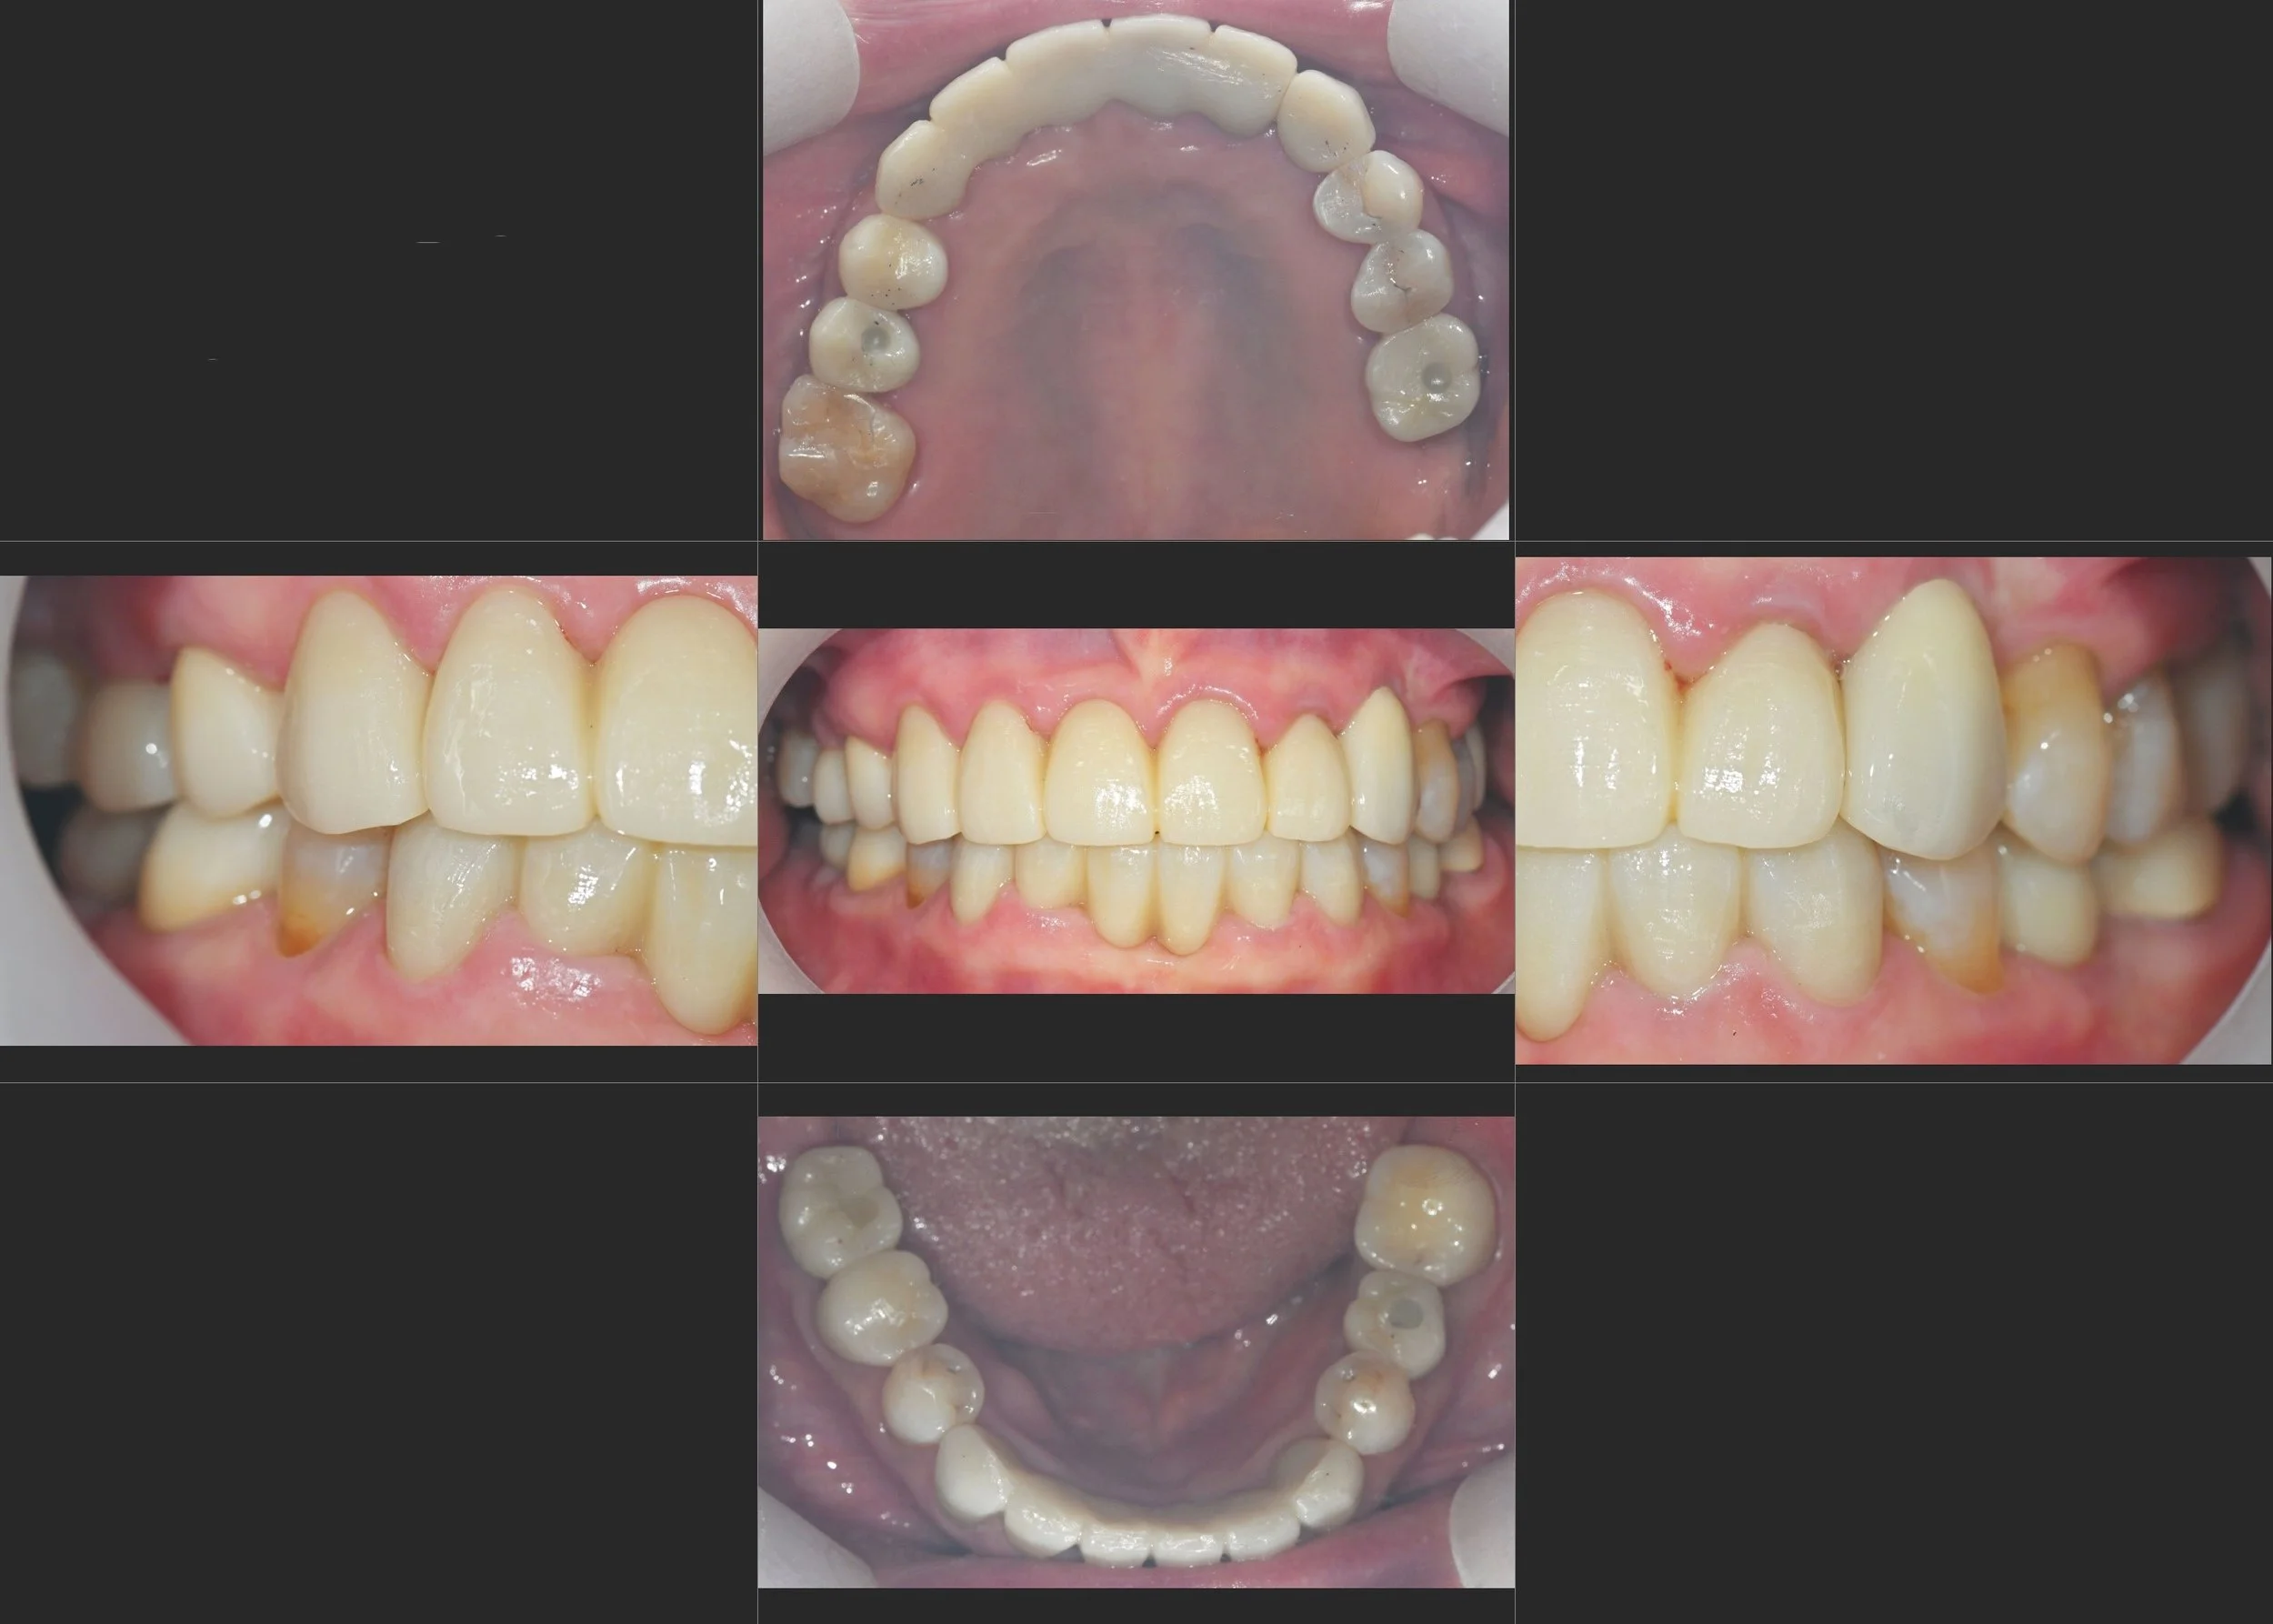

INTRA ORAL - AFTER

A key aspect of this case was establishing a new, functional vertical dimension of occlusion. The final prostheses were fabricated to provide stable posterior occlusion on the premolars and first molars. Although the second molars were omitted due to cost considerations, this arrangement successfully achieved a stable posterior stop, fulfilling the patient's functional requirements and providing a satisfactory esthetic outcome.